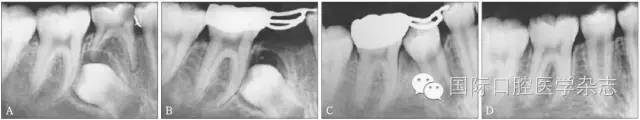

圖3為一因“乳磨牙爛牙”前來就診兒童的X線片檢查。影像學(xué)檢查顯示:第二乳磨牙近中深齲,近遠(yuǎn)中牙根吸收均不明顯,但遠(yuǎn)中根尖病變引起了第二前磨牙萌出方向的改變。臨床處置:及時(shí)拔除了齲壞的第二乳磨牙,制作第一恒磨牙帶環(huán)絲圈間隙維持器,3個(gè)月后復(fù)診,X線片顯示第二前磨牙萌出方向逐漸正向調(diào)整;6個(gè)月后復(fù)診,第二前磨牙基本正位萌出;1年后復(fù)診,第二前磨牙調(diào)整到位。從圖3的病例可以看出:乳磨牙根尖周病變會(huì)引起恒牙萌出方向的改變,出現(xiàn)咬合紊亂的潛在性表現(xiàn),但臨床上通過去除病灶牙與簡單的間隙維持、未實(shí)施牽引助萌即糾正了該病例潛在性的咬合紊亂發(fā)生。

A:下頜第二乳磨牙近中齲,X線片顯示遠(yuǎn)中根尖周病變引起繼承恒牙萌出方向改變;B:擬及時(shí)拔除病變的下頜第二乳磨牙,行間隙維持;C:拔除病變的下頜第二乳磨牙間隙維持后一段時(shí)間,繼承恒牙萌出方向發(fā)生正向改變;D:繼承恒牙正位萌出。

圖3 乳牙根尖炎癥引起繼承恒牙萌出方向改變的典型病例

Fig 3 Typical case oferuptive direction change caused by periapical infection of primary tooth